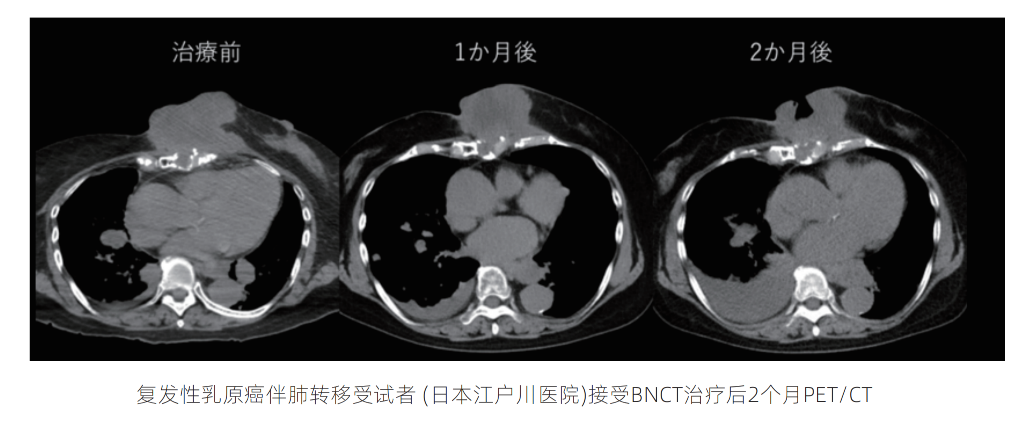

乳腺癌

复发性乳腺癌伴肺转移的大体积肿瘤患者, 经BNCT照射后2个月肿瘤形成空洞、体积大幅缩小, 虽胸腔积液增加但全身状态稳定;乳腺癌相关探索性临床试验显示, 受试者肿瘤病灶缩小且无放射性肺炎不良反应,验证了加速器BNCT治疗乳腺癌的安全性与有效性, 为乳腺癌患者及医疗界带来新希望。